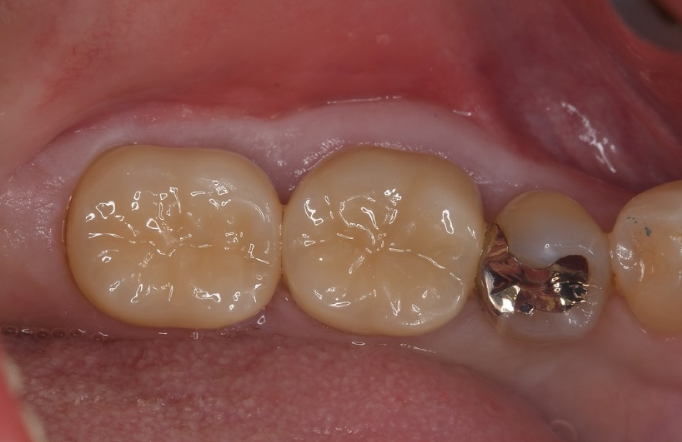

症例3

| 項目 | 詳細 |

|---|---|

| 患者様データ | 40代 女性 |

| 来院時の主訴 | 「歯がグラグラする。」 |

| 医院の診断 | 重度の歯周病、夜間歯ぎしり習慣 |

| 通院期間 |

1年 |

| 来院回数 | 8回 |

| 治療費 | 総額:220,000円(税抜) 【内訳】 歯周組織再生療法220,000円(費用は範囲によって異なります。) |

| リスクと副作用 | メインテナンスが必要、正しい歯磨き習慣が必要不可欠 |

| ここがこだわりのポイント!☝ | 痛みや手術時間が最小限となるよう、マイクロスコープを使用して小さい傷口の術式でオペを行なっています。 |